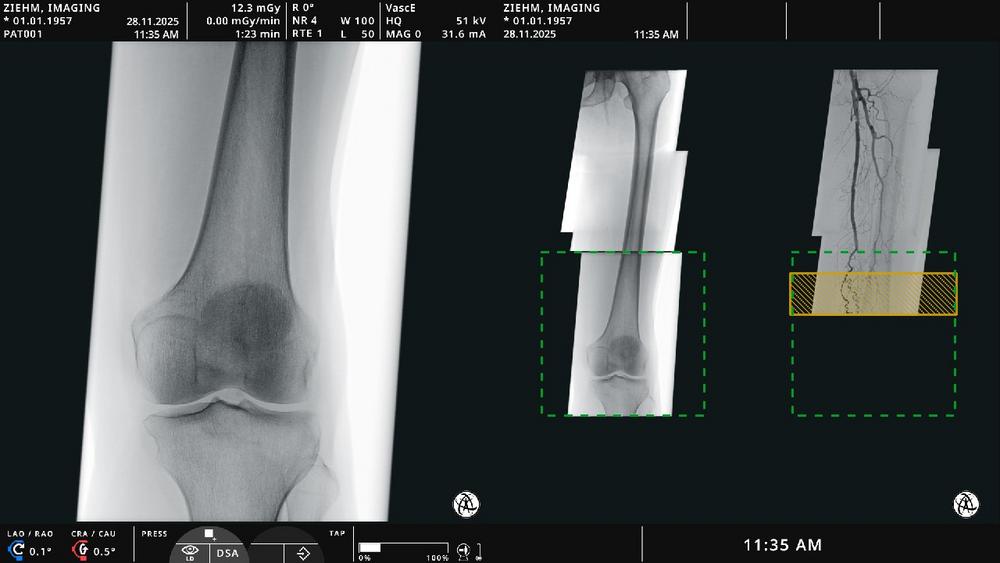

Endovascular Navigation Peripheral ermöglicht die Panorama-Erstellung bei peripheren arteriellen Verschlusskrankheiten, indem Fluoroskopie- und Angiographiebilder zu einer vollständigen, aktuellen Übersicht zusammengefügt werden. Thrombotische und stenotische Bereiche können einfach identifiziert und markiert werden. „Live-Fluoroskopiebilder werden präzise mit dem angiographischen Panorama fusioniert – so können Anwendende mit optimaler Orientierung und ohne zusätzliches Kontrastmittel navigieren“, erklärt Martin Törnvik, Vice President Global Sales & Marketing. Algorithmen auf Basis künstlicher Intelligenz sorgen für automatische Bildfusion. Diese passt sich in Echtzeit an Bewegungen von Patientin bzw. Patient, Tisch oder C-Bogen an. Die Lösung ist vollständig in den Ziehm Vision RFD Hybrid Edition3 (Cardio) und den Ziehm Vision RFD 3D integriert.